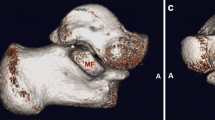

The coalitions were classified into four main types according to the shape and nature of the coalition: I, inferiorly overgrown talus or superiorly overgrown calcaneus; II, both talus and calcaneus overgrew; III, a coalition with an accessory ossicle; (I-III types are non-osseous coalition) IV, complete osseous coalition. On the coronal images of CT, the shape and nature of the coalitions could be observed. Then each type was further divided into three subtypes according to the articular facets involved. A, the coalition involving the anterior facets; On the coronal images of CT, the coalition could only be found anterior to the images of the tarsal sinus for this subtype. M, the coalition involving the middle facets. The subtypes could be identified through the coronal images of CT of the tarsal sinus. P, the coalition involving the posterior facets. On the coronal images of CT, the coalition could only be found posterior to the images of the tarsal sinus. For the coalitions involving the posterior facets only, the open of the sinus tarsal was obvious on a 3D reconstruction image. While for the coalitions involving the middle and posterior facets, the open of the sinus tarsal could not be seen on a 3D reconstruction image (Figs. 1, 2, 3, 4, 5, 6, 7, 8 and 9).

Rozansky et al. [17] depicted the features of coalitions on the 3D construction image, however, they didn’t emphasize the open of the tarsal sinus. In the current study, the open of the tarsal sinus could be found in the subtype-P coalitions on a 3D construction image, while for subtype-MP and AMP, it could not be found. So, we can also distinguish the facets that the coalitions involve from a 3D construction image.